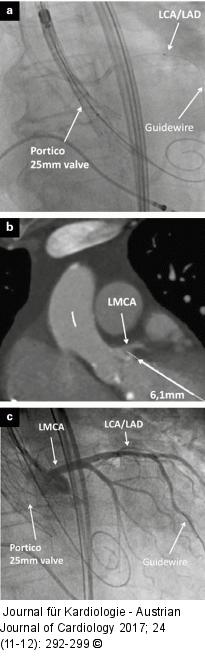

Abbildung 2a-c: Valve implantation Tiefenthaller G, et al. (a): Guidewire protected LCA during valve implantation; (b): Planning CTLMCA; (c): Post-valve implantation angiogramm shows open LCA. |

Tiefenthaller G, et al. (a): Guidewire protected LCA during valve implantation; (b): Planning CTLMCA; (c): Post-valve implantation angiogramm shows open LCA. |